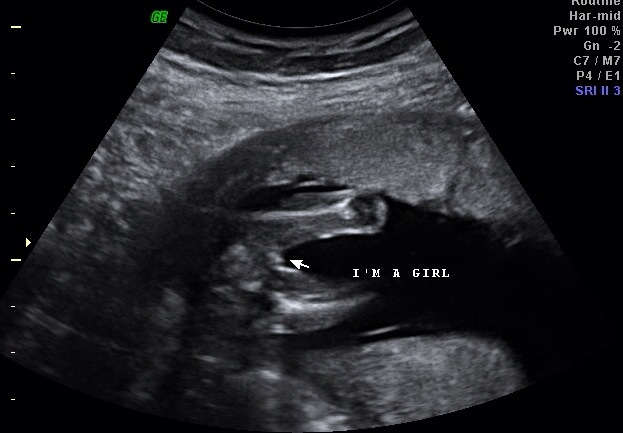

УЗИ, КТГ, доплерКогда нам было 16 недель мы пошли на

узи и нам сказали что у нас 100% девочка

но по фото мне кажется не похоже на

девочку. Вот хочу что бы вы посмотрели

ведь часто бывает что ошибочно.